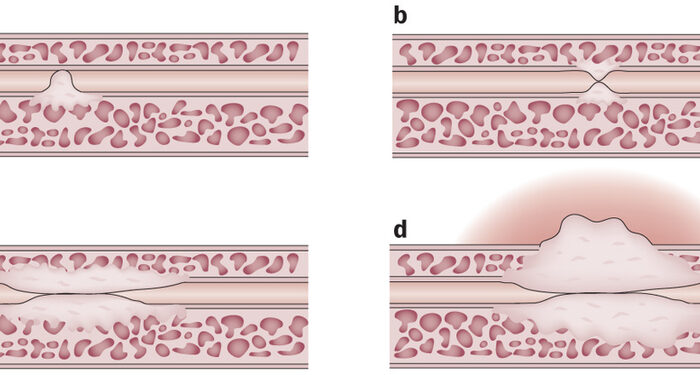

- Histeroscopia diagnóstica y terapéutica.

- Cirugías ginecológicas ambulatorias (ej. extirpación de quistes, miomas, lesiones benignas).